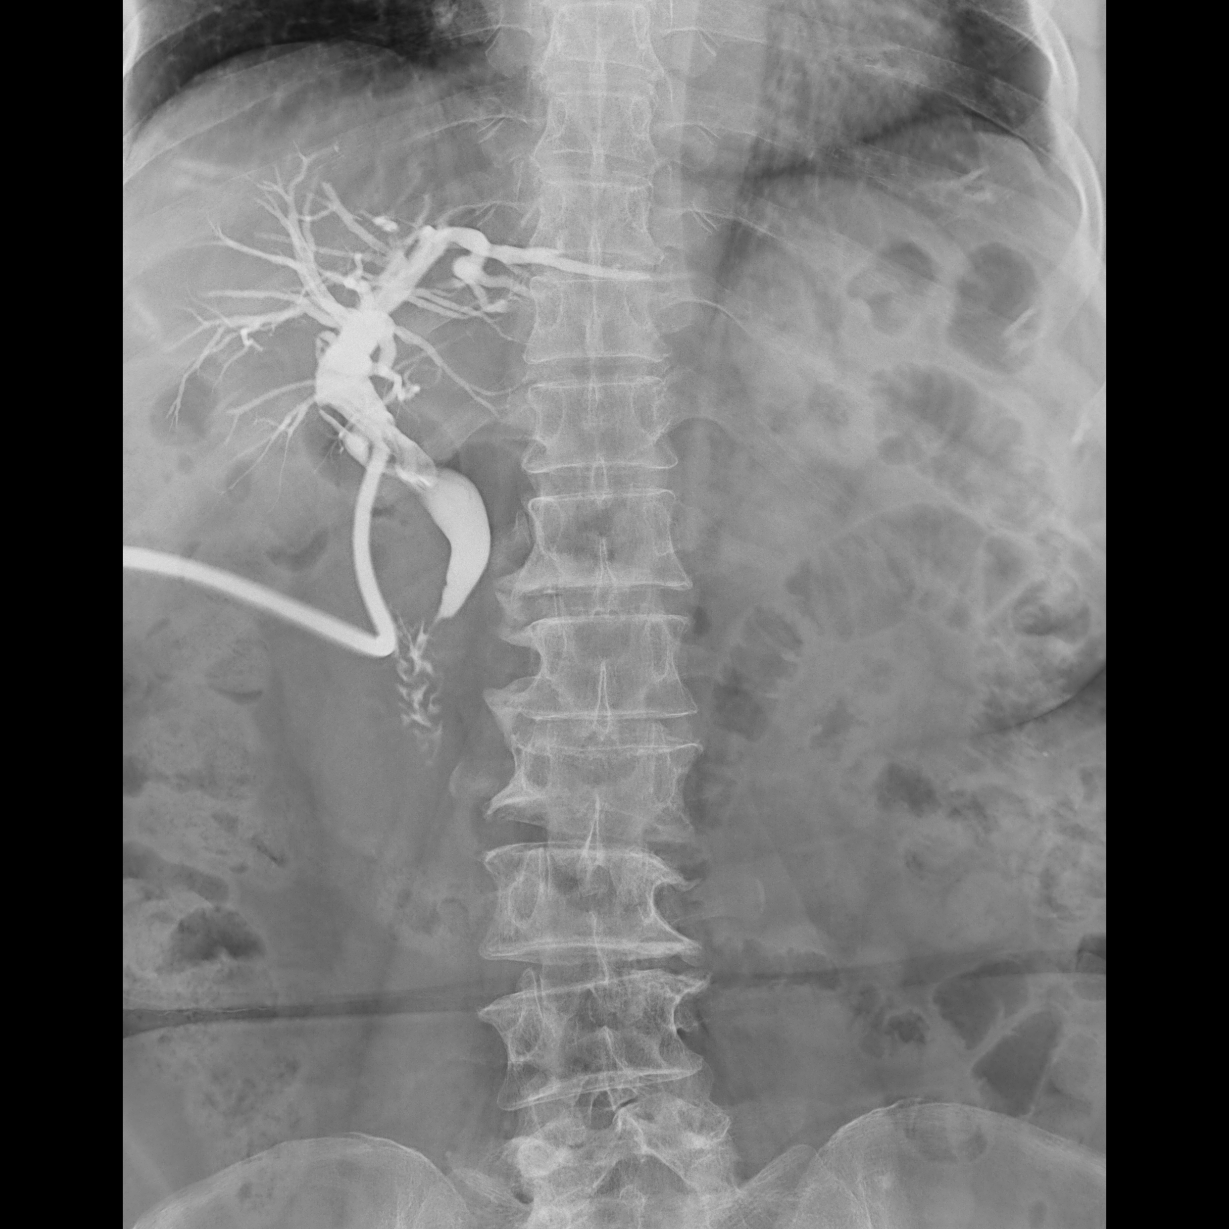

腎盂造影